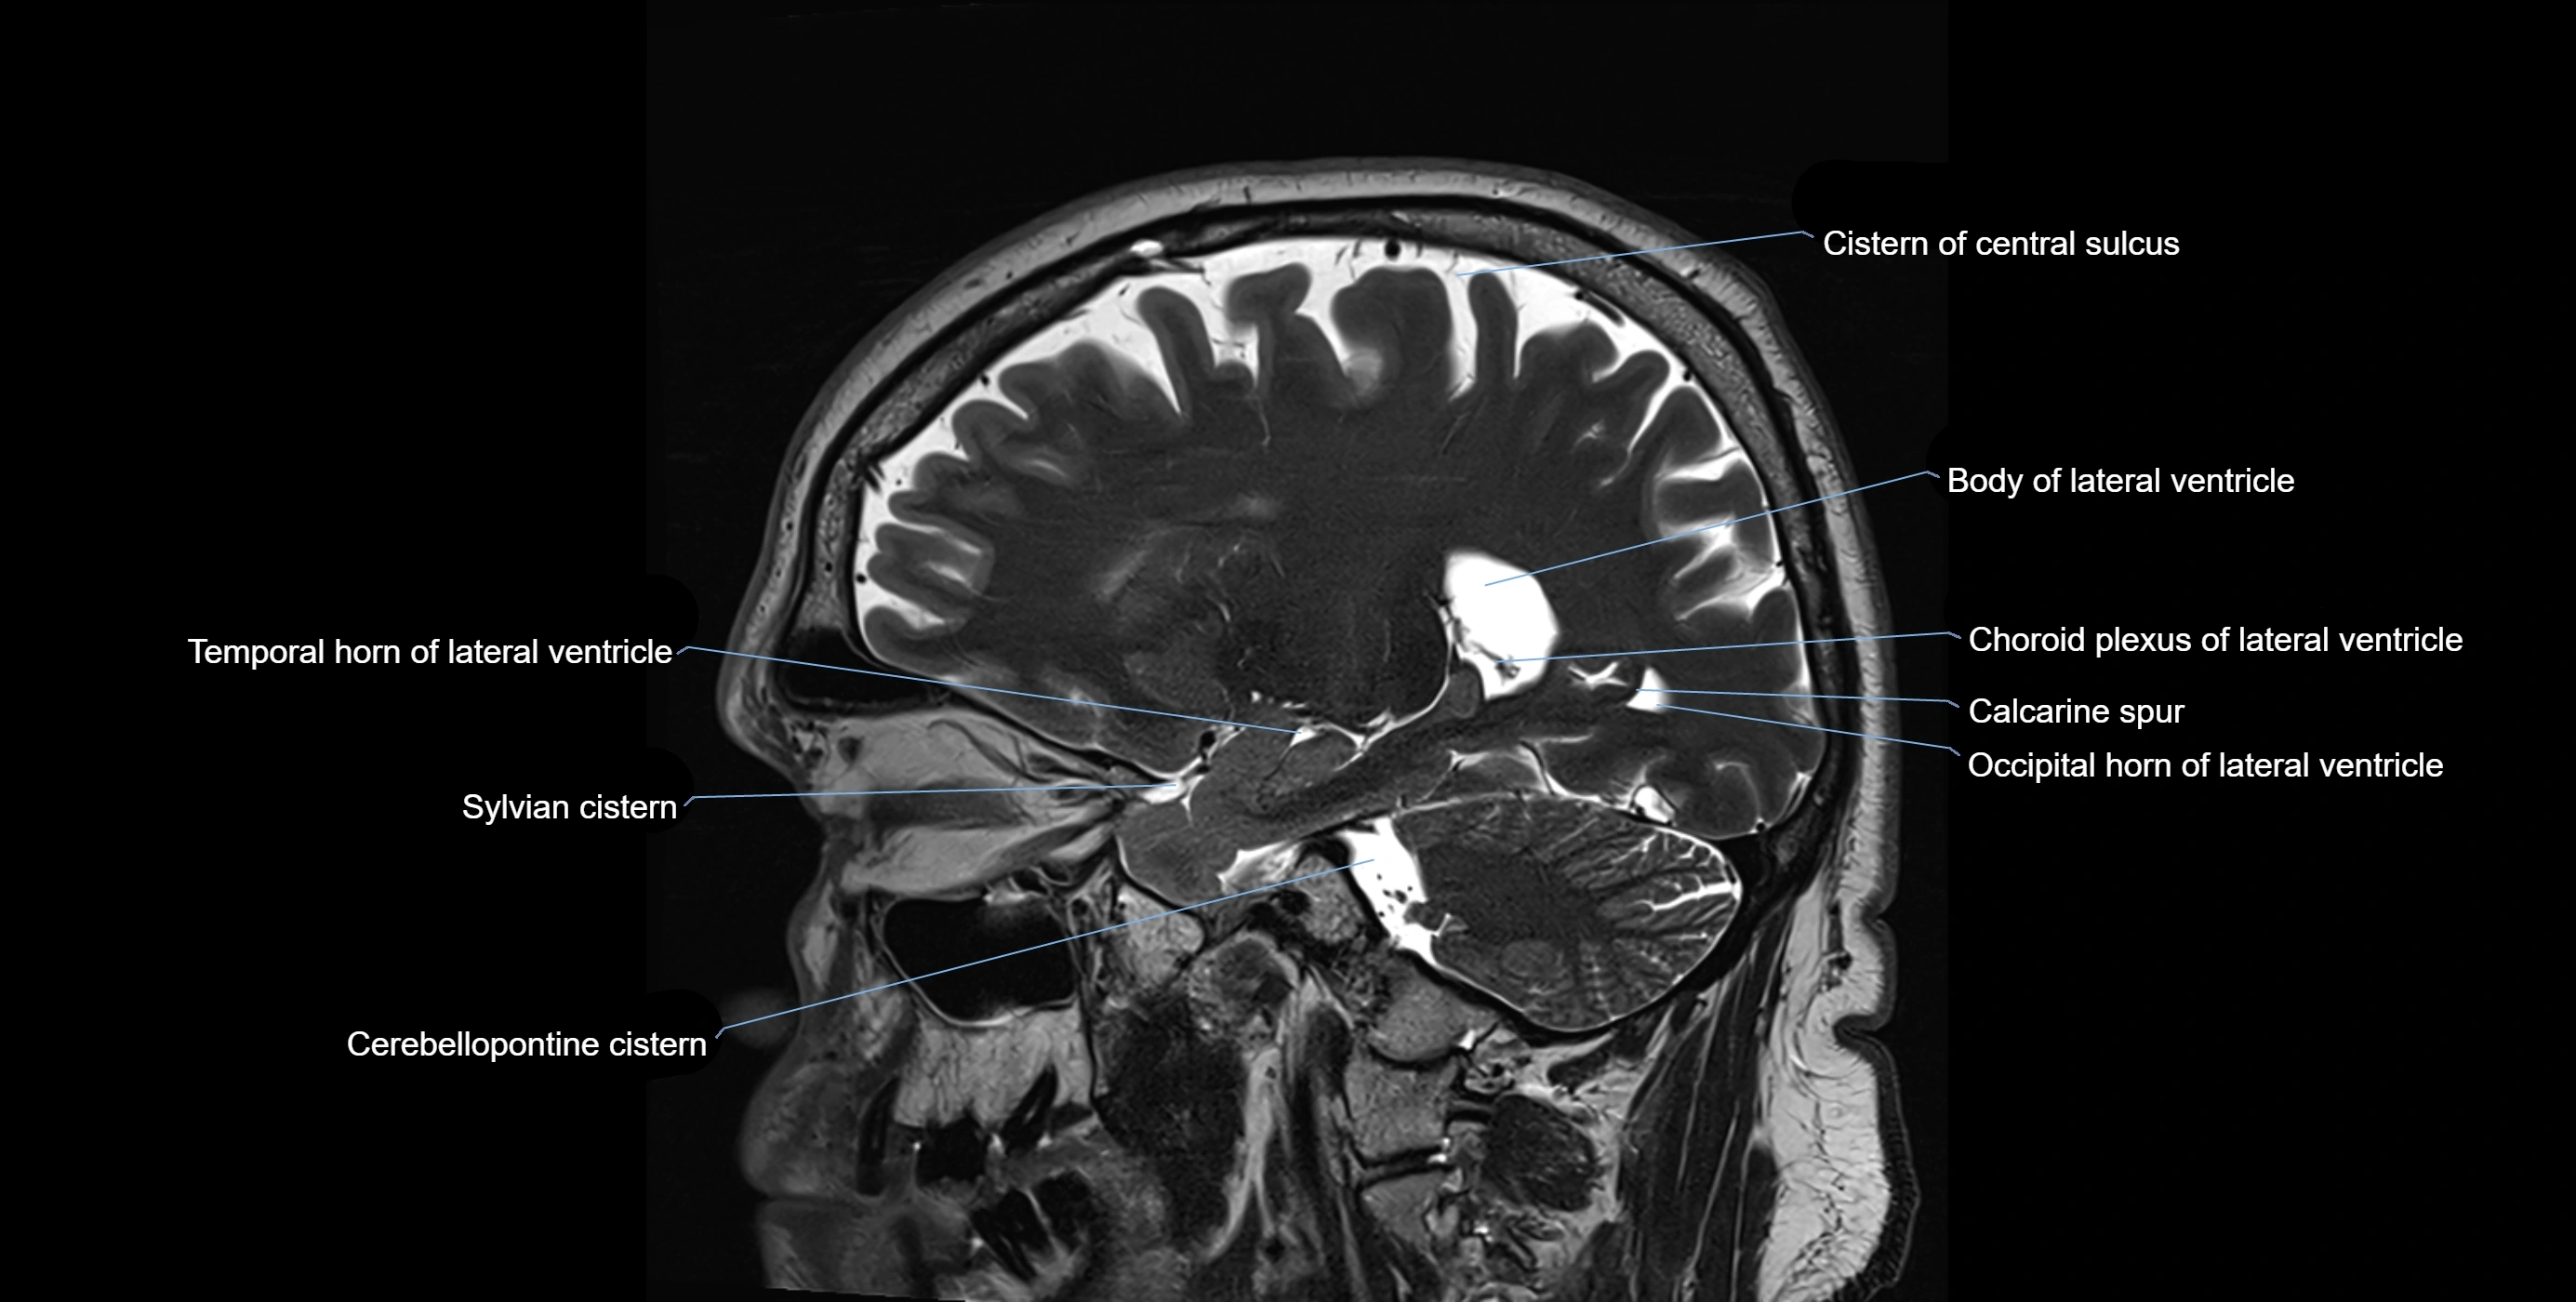

MRI images

image